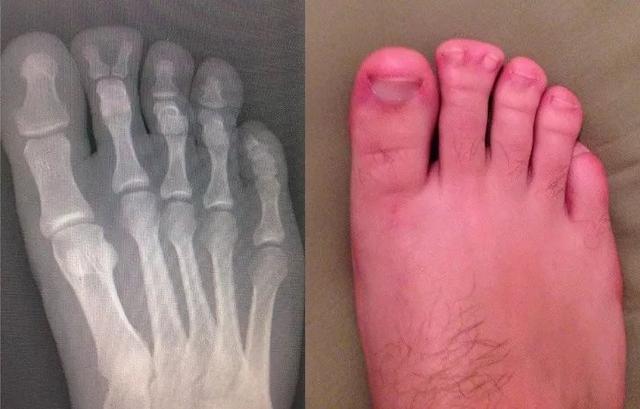

分叉的脚趾